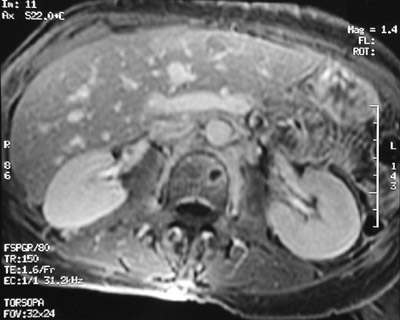

The rounded lucency seen here in a vertebral body with T1 weighted MRI scan is one focus of plasma cells in a case of multiple myeloma. This patient had lesions in multiple sites. Another lesion is seen below with T2 weighted MRI scan.